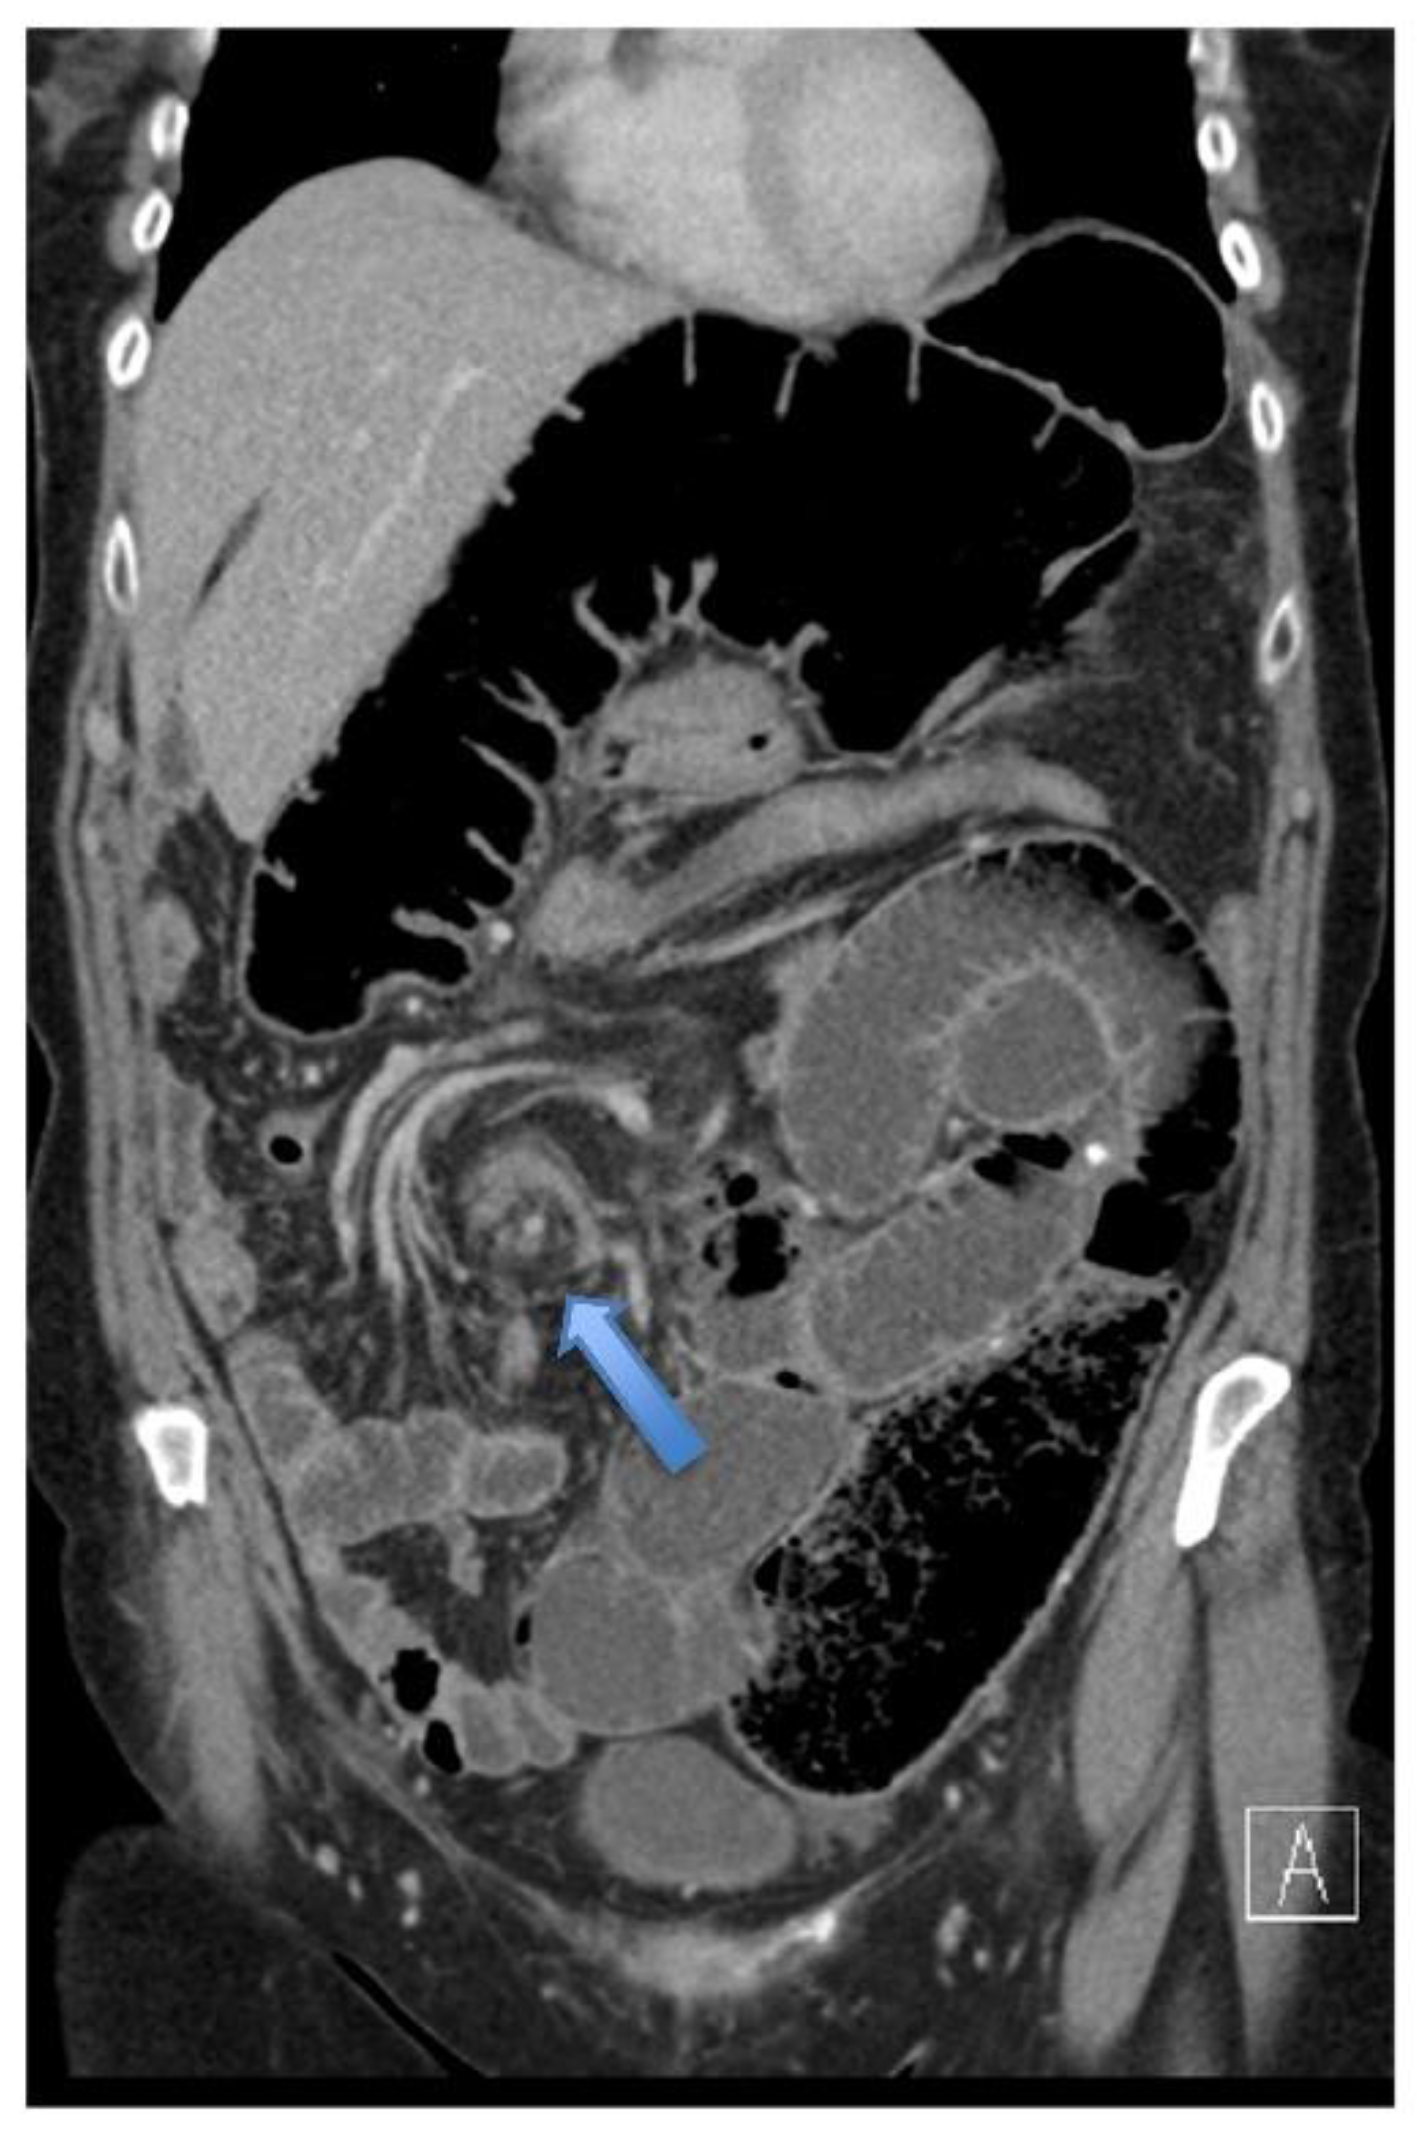

4.4.2. Computerised Tomography (CT) Scan

| Whirl sign | 12 (80%) | |

| Split-wall sign | 13 (86.6%) | |

| X-marks-the-spot sign | 14 (93.3%) | |

| Double transition point | 13 (86.6%) | |

| Ileocaecal twist | 13 (86.6%) | |

| Central appendix | 11 (73.3%) |